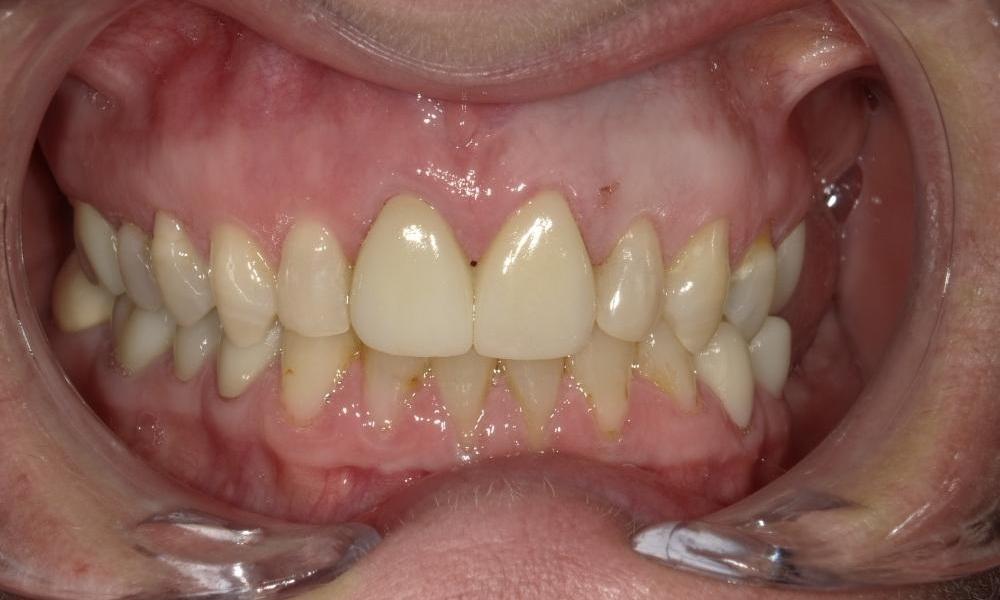

What a big difference 2 crowns can make!

Patient does not like the look of her old front crown and who could blame her.  The old crown was done a long time ago and the gum has receded, causing metal margin of the crown to show, and extensive amount of root surface exposed.  Due to having a previous root canal therapy, the tooth has gotten darker over time as well.  For cosmetic reasons, we decided to crown both front teeth to create better symmetry and enhance esthetics.  We do not use metal in our crowns so we do not need to worry about a dark crown margin showing again in the future.  At the end, we picked a crown material that has just enough translucency to look natural but not too much where the darkness of the tooth would show through.  Patient was very happy with the results and we were happy to have made a big difference in this patient's smile.